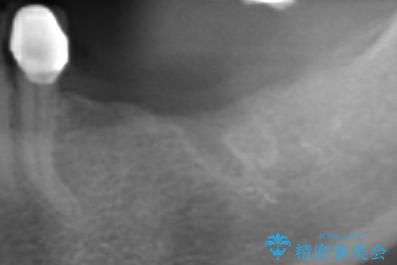

- 歯を虫歯により失い、「とりあえず入れ歯を入れたが,とにかく噛めず食事が全く楽しくない」またしっかりと噛みたいと希望され来院されました。

入れ歯を外し、またしっかりと噛んで食事を楽しめるようになるためにインプラントによる治療を計画します。

インプラントを埋入することで入れ歯のように取り外しをする必要がなくしっかりと噛めるような状態になり、大変治療結果に満足していただくことができました。